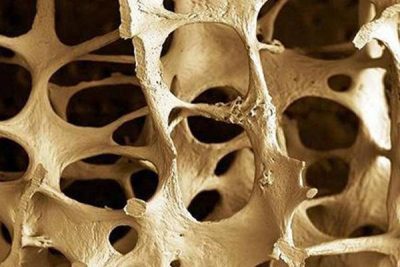

Immagine:osteoporosi.Credit: Public Domain.

Il mantenimento di un osso sano dipende da un equilibrio tra gli osteoblasti, che secernono i materiali necessari per formare nuovo osso e gli osteoclasti, che assorbono il vecchio materiale osseo per far posto al nuovo. Un’interruzione in questo equilibrio in un modo o nell’altro può provocare danni alle ossa. Nel caso dell’osteoporosi, gli osteoclasti iperattivi consumano l’osso più velocemente di quanto possa essere riformato, causando ossa meno dense e più suscettibili alle fratture.

Con queste informazioni, i ricercatori di questo studio, il cui autore principale è Wei Yu, MD, Ph.D., che lavorava come visiting scholar alla Penn Medicine, hanno studiato topi con carenze di RANKL nei loro MALP. Dal momento in cui quei topi hanno compiuto un mese di vita, i ricercatori hanno visto una densità maggiore dal 60 al 100% dei componenti spugnosi delle ossa lunghe (come il femore) e delle vertebre, qualcosa che i ricercatori hanno definito “un aumento drastico” rispetto alla tipica massa ossea di topo.